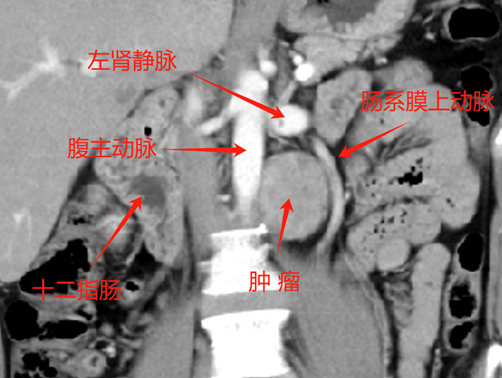

l CT:腹膜后腹主动脉旁软组织密度肿块,边界清,约4.2*4.3cm,密度不均,增强扫描皮髓质不均匀强化,实质期强化稍低,排泌期进一步减低。左肾2.0*2.3cm囊状低密度影。结论:左侧腹膜后占位,副神经节瘤?,左肾囊肿

6、 肾门下方、输尿管内侧和腹主动脉旁探及本次腹膜后肿物,目测尺寸5*5.5cm。复习CT可见肿瘤与腹主动脉关系密切,明显增强提示其血供丰富。术前阅片发现,肠系膜上动脉主干因肿瘤推挤向左侧移位。完整剥离减少出血是本次手术的重难点。且周围靠近十二指肠,操作中注意保护。